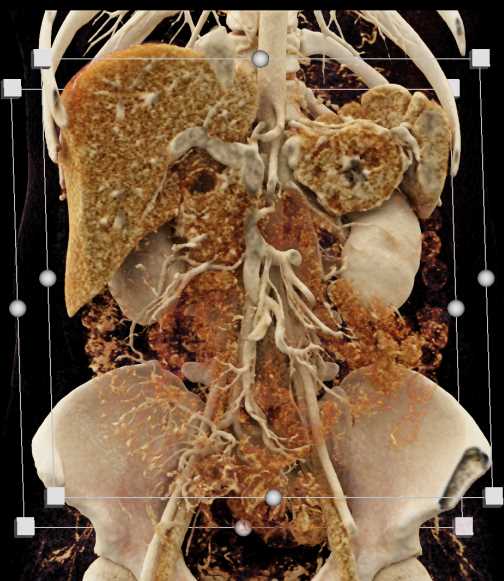

Neuroendocrine Tumor Pancreas